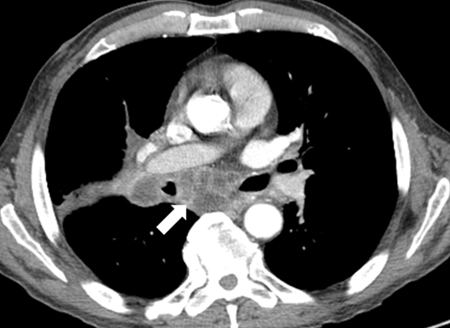

Linfadenopatia necrótica mediastinal

Dos acervos do Dr. Mario Gasparri e do Dr. Nicholas Choong